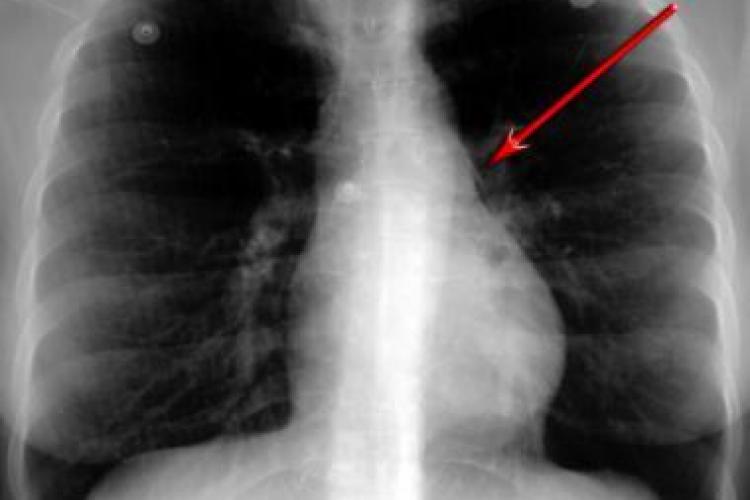

Băiețel de 2 ani, în stop respirator la Spitalul de Copii! Părinții s-au șocat de ce avea în plămâni

Un copil de 2 ani a fost adus în stop cardio-respirator la Spitalul de Copii din Cluj, fiind în stare deosebit de gravă.